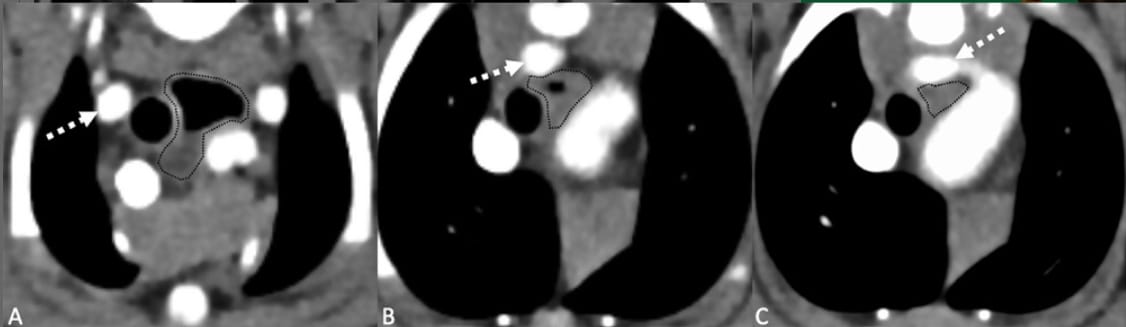

Postcontrast transverse CT images in a soft tissue window (WW 400, WL 40) showing a representative example of esophageal dilation (A) and compression (B, C) in a patient with an aberrant right subclavian artery (ARSA, depicted with the dashed arrow). Left is to the right of the image. (A) Cranial to the heart base the esophagus (encircled by the dashed black line) is dilated with gas dorsally, and fluid attenuating content ventrally. (B, C) As the ARSA passes dorsally, the esophageal diameter is markedly reduced compared with image (A). This patient had clinical signs attributable to the ARSA.